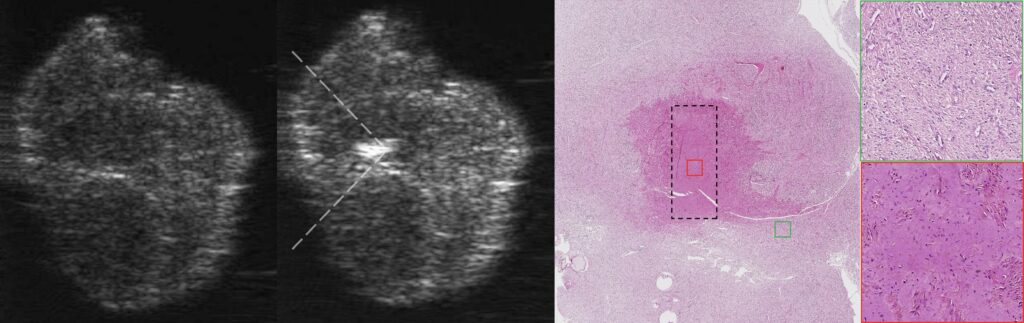

Недавно нами впервые была продемонстрирована принципиальная возможность механического разрушения лейомиомы матки человека ex vivo методом гистотрипсии с кипением, при этом ткань в области воздействия была ликвифицирована до субклеточных фрагментов, что было подтверждено гистологически.

На данный момент в Лаборатории ведутся исследования на большей выборке препаратов для изучения отклика различных типов миом матки на механическое разрушение методом гистотрипсии с кипением, влияния их упругих свойств на этот отклик, а также для определения диапазона оптимальных параметров воздействия для эффективного и быстрого разрушения таких новообразований.